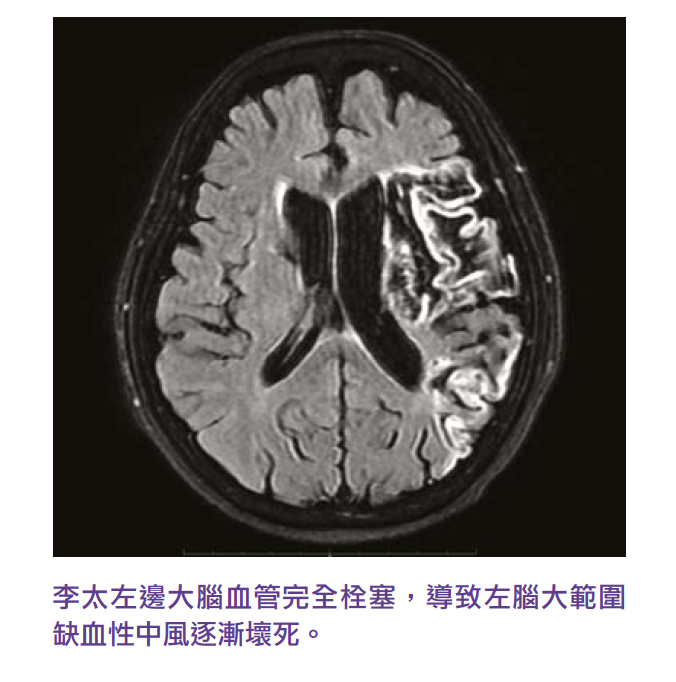

Ms. Li, a 69-year-old housewife with history of diabetes, high cholesterol and high blood pressure, has been following up and taking medication in public hospitals. When she woke up one morning two years ago, her children found that she had difficulty speaking and that her right hand and foot were weak, so they urgently called an ambulance to take her to the emergency room. After a CT scan, the doctor’s diagnosis was an ischemic stroke in the left side of the brain. During the two-week of hospitalization, Ms. Li’s daugther found that her mother’s condition not only did not improve, but also deteriorated, gradually becoming unable to speak, and her right hand and foot were gradually unable to move, so they admit their mother to a private hospital for continued care. Detailed brain MRI showed that the blood vessels in Li’s left brain were seriously damage, resulting in a large necrosis of her left brain due to ischemic stroke, so that her speech ability and the strength of her right hand and foot became worse

After three months of hospitalized with stroke rehabilitation, through specialized drugs, physiotherapy, acupuncture, DIRECT current stimulation treatment and brain TMS treatment, Li’s right foot strength was significantly restored, from complete inability to move, to the right foot ability to walk with the assistance of equipment, and the language ability to communicate and talk fluently with her children. After being discharged from the hospital, Ms. Li continued to receive medication, brain TMS therapy and physical therapy, and her walking ability and language skills continued to improve. The main reason for Li’s cerebral vascular stroke is caused by poor control of high cholesterol. She needs to take high-dose cholesterol drugs and platelet drugs for a long time to prevent cerebral blood vessels from degenerate and prevent another stroke. Today Ms. Li is only moderately disabled, able to use cane to walk on her own, and can continue to live at home under the care of a domestic helper.